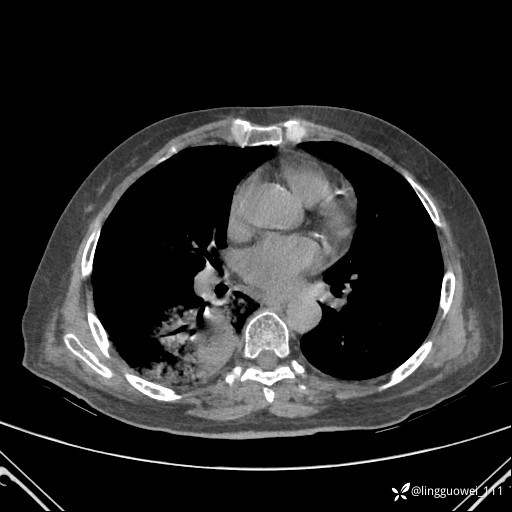

CT平扫: